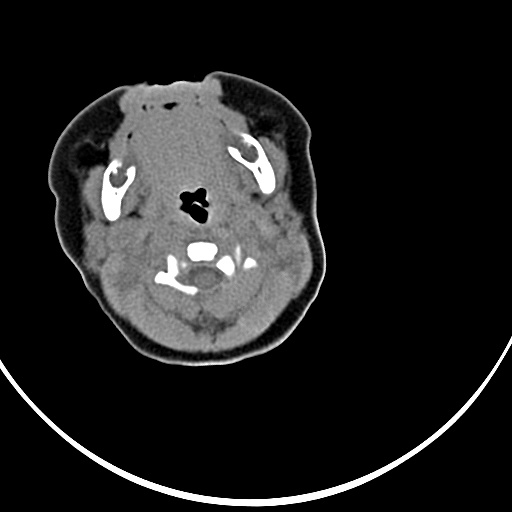

患者,男,1月,出生后一月,无明显诱因出现颈部左前方肿块。体检:左侧颈部轻度凸起包块,触之较硬。

患者,男,1月,左经部轻度凸起包块,质硬。

病灶与左侧胸锁乳突肌分界不清,软组织密度,不似囊性改变,从病人的年龄及病变性状首先要除外先天性斜颈(肌性斜颈)可能。

左侧胸锁乳突肌肿大,考虑产伤所致

胸锁乳突肌挛缩(斜颈)?